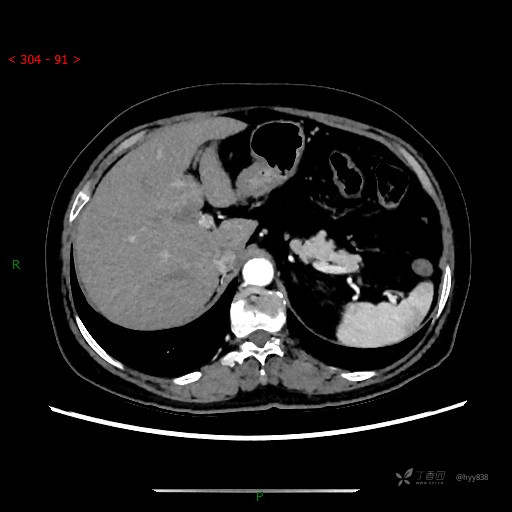

静脉期